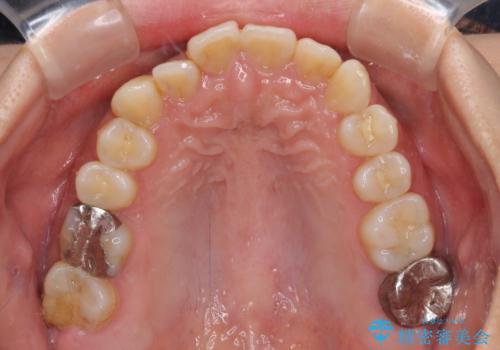

前歯のデコボコとクロスバイト インビザラインによる矯正治療

- 上下のクロスバイトと前歯のデコボコを気にして来院された患者様です。

骨格的に下顎がやや前方にあり、奥歯にクラウンが装着されているため、矯正治療後半の不安定な咬み合わせを避けるのであればワイヤー矯正がおすすめとなりますが、希望によりインビザラインにて治療を行うこととしました。

インビザラインを用い、IPR(歯と歯の間を削る)と歯列全体を拡大させることで、歯並びを整えていくこととしました。

懸念されたとおり、右下のクラウン部分が全く咬み合わず、仕上げの段階で治療期間が長くなりました。